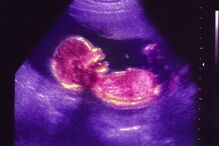

Uma espécie de placenta artificial está a ser desenvolvida no Hospital Infantil de Filadélfia, na Pensilvânia, nos Estados Unidos da América. O chamado ambiente extra-uterino para o desenvolvimento do recém-nascido não tem o objetivo de desenvolver fetos, substituindo uma gravidez, mas apenas auxiliar bebés prematuros a completarem o tempo gestacional.

O sistema respiratório é bastante afetado aquando do nascimento prematuro dos bebés com, por exemplo, 22 ou 23 semanas de gestação, que não estão prontos para respirar autonomamente. A ideia por detrás dos úteros e das placentas artificiais é "retirar todos os pulmões da equação", explicam os médicos, dando tempo para que o bebé continue a desenvolver-se num ambiente seguro até que esteja pronto para respirar pela primeira vez.